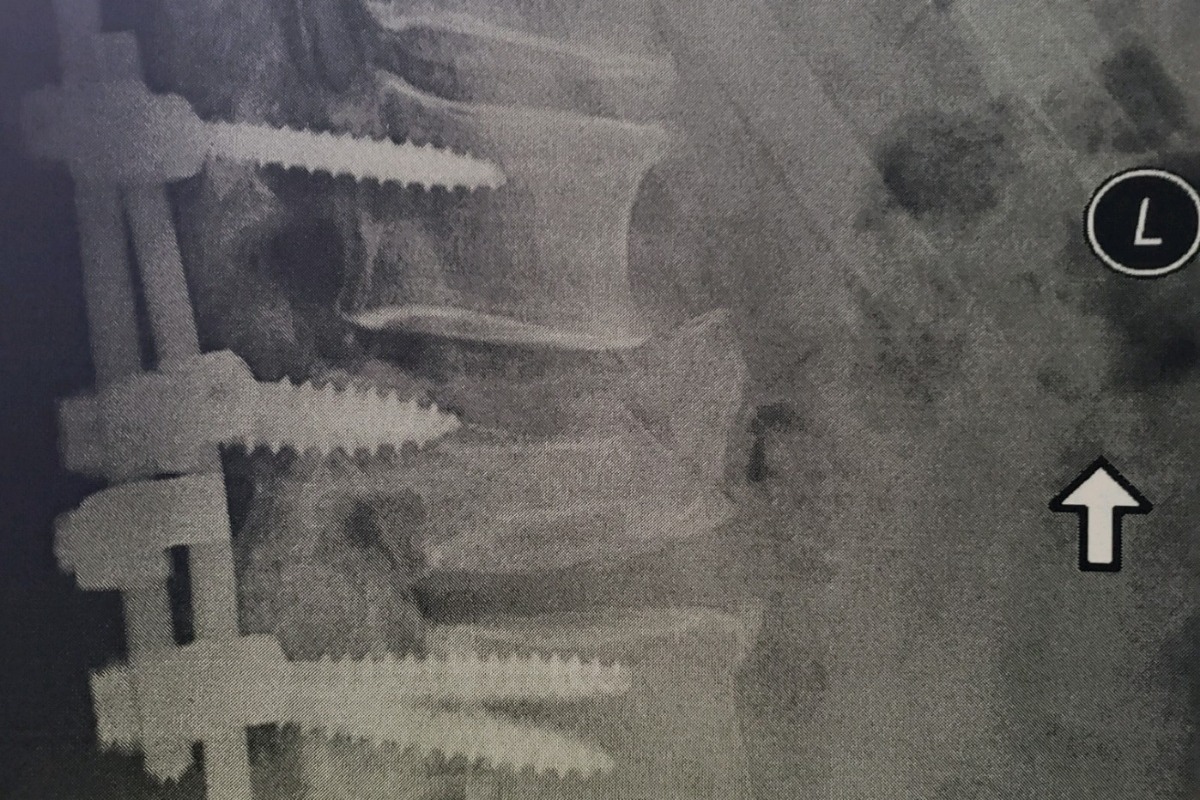

-1998 Broke his L4 & L5 vertebrae. A fusion cage was placed in his back & he spent 2 years in a body cast due to his bones not growing properly… Also, an issue that stemmed from radiation

-1998 Broke his L4 & L5 vertebrae. A fusion cage was placed in his back & he spent 2 years in a body cast due to his bones not growing properly… Also, an issue that stemmed from radiation